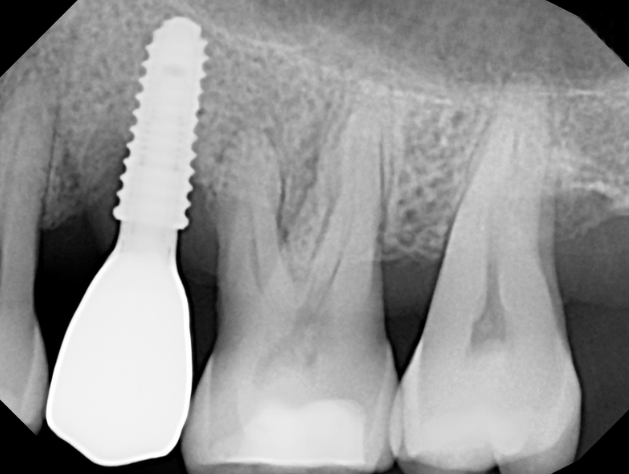

The LAPIP protocol offers a minimally invasive, laser-based method for treating peri-implantitis—the inflammation and bone loss that threatens the stability of dental implants. Using the same PerioLase® MVP-7™ technology as LANAP, LAPIP precisely targets infected tissue and harmful bacteria surrounding the implant while protecting healthy gum and bone. This allows the body to naturally rebuild lost support and helps save implants that would otherwise be at risk of failure. With no cutting or sutures required, LAPIP provides a gentle, highly effective alternative to traditional peri-implant surgery.

LAPIP™ (Laser-Assisted Peri-Implant Procedure) is a minimally invasive laser treatment designed to save ailing or failing dental implants caused by peri-implantitis. Using the PerioLase® MVP-7™ Nd:YAG laser, the protocol targets inflamed, infected tissue and titanium corrosion contaminants while preserving healthy gums and bone. This tissue-sparing approach promotes bone regeneration around the implant and offers a more comfortable treatment with less bleeding, swelling, and downtime than traditional surgery.

Traditional gum and implant surgery often requires cutting into the tissue, lifting flaps, and stitching the area closed afterward. These methods can increase trauma, bleeding, swelling, and longer recovery times. LANAP and LAPIP eliminate the need for scalpels or sutures by using the PerioLase® MVP-7™ laser to selectively remove infection while protecting healthy gum and bone—whether around natural teeth or dental implants.

LANAP and LAPIP have transformed how professionals treat gum disease and peri-implantitis. Instead of removing tissue, the protocols support natural healing by creating an environment where gums can reattach and bone can regrow. LANAP helps save natural teeth suffering from periodontal disease, while LAPIP can rescue implants that might otherwise fail—offering patients a predictable, minimally invasive alternative to traditional surgery.